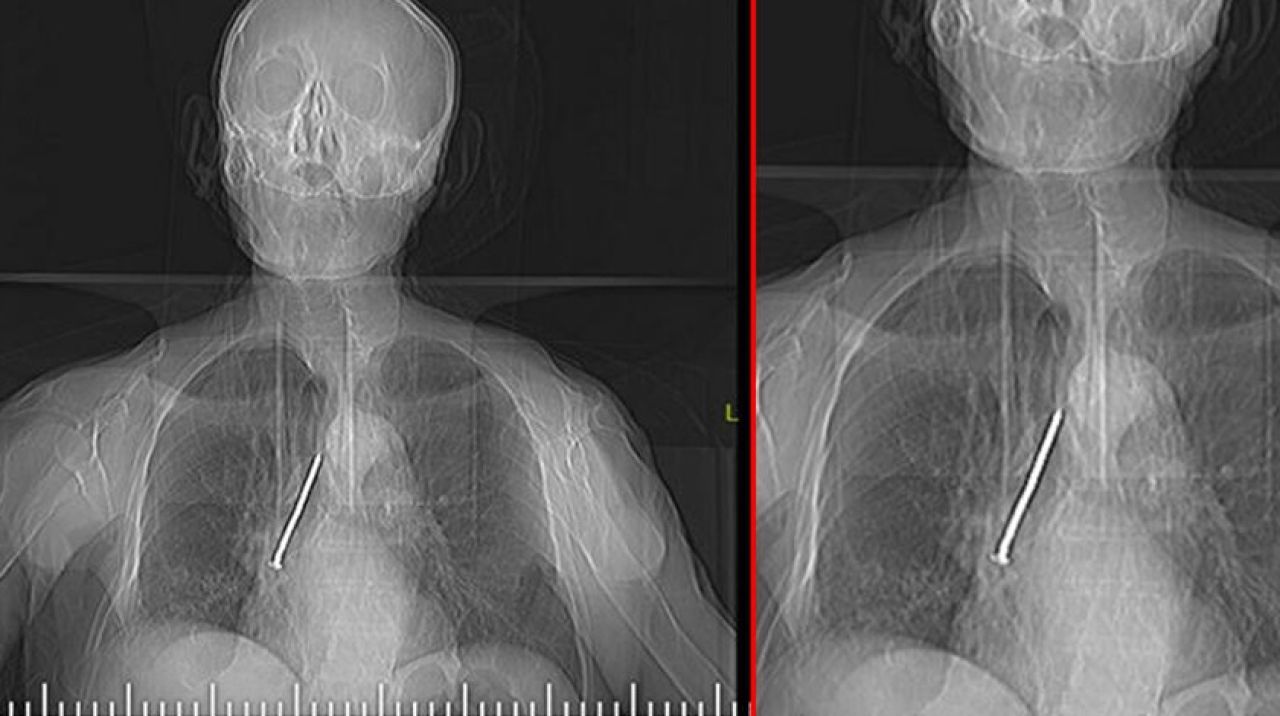

Keko Ateş, öksürük ve nefes darlığı şikayetiyle Fethi Sekin Şehir Hastanesi'ne başvurdu. Yapılan tetkik ve muayenelerden sonra Ateş'in nefes borusunda çivi olduğu tespit edildi. Hastanın hayatını tehlikeye atan bu durumun giderilmesi için Ateş, Göğüs Cerrahi Uzmanı Dr. Öğr. Üyesi Murat Kılıç tarafından operasyona alındı. Soluk borusun içerisinde ve sağ akciğer içerisine doğru kaçmış olan 10 santim uzunluğundaki çivi, 'Rijit Bronskoskopi' işlemiyle çıkarıldı.

Dr. Öğr. Üyesi Murat Kılıç, Larenks kanseri olan Ateş'in, 24 yıl önce Total Larenjektomi ameliyatı sırasında boynundan nefes borusuna açılan açıklığı temizlemek için kullandığı çivinin soluk borusuna kaçtığını anlattı. Dr. Öğr. Üyesi Kılıç, "Bu nedenle gelişen öksürük ve nefes darlığı şikayeti ile önce başka bir sağlıkmerkezine başvuran, ardından Fethi Sekin Şehir Hastanemiz Göğüs Cerrahisi Kliniği'ne yönlendirilen hastaya çektiğimiz tomografide soluk borusu içerisinde ve sağ akciğer içerisine doğru kaçmış olan bir çivi olduğunu tespit ettik.

Bunun üzerine hastamızı acil olarak ameliyata aldık. Uyguladığımız Rijit Bronskoskopi işlemi ile nefes borusundaki 10 santimlik çiviyi başarılı bir şekilde çıkardık. Hastamızı ameliyat sonrası bir süre serviste takip ettikten sonra gün içerisinde şifa ile taburcu ettik" dedi.